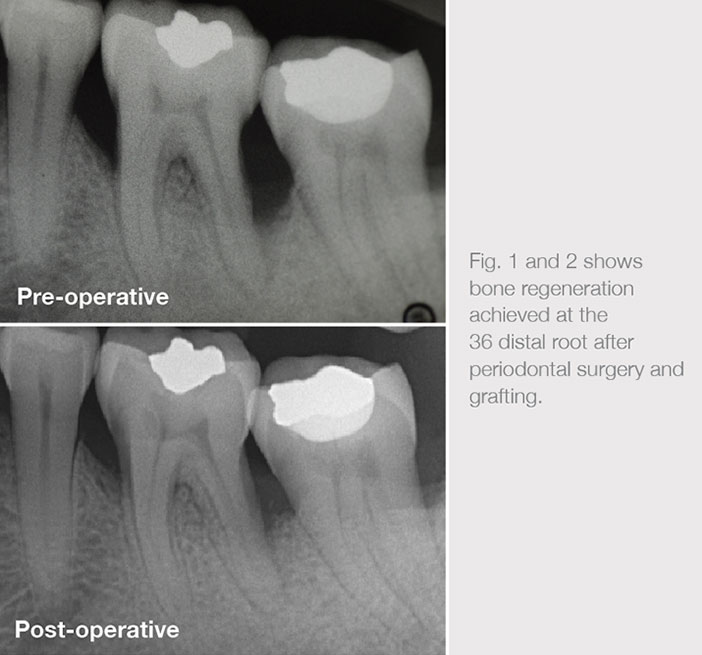

Advanced periodontal problems can be successfully treated with periodontal surgery. A modern approach employs microsurgical techniques combined with the application of regenerative materials. The patient above had a recurrent abscess at the 36 with advanced bone loss to the apical third of the apex. The aim of therapy was not only to resolve the acute infection, but to improve the prognosis of the tooth.

Periodontal examination revealed up to 9mm probing pocket depths at the 36 as well as a deep intrabony defect at the distal aspect. A modern minimally invasive flap design that preserved the papilla was utilized to gain access to the intrabony defect. The tooth was carefully debrided, and the root surface was treated with EDTA. Emdogain gel was then applied and a xenograft (Bio-Oss) was then used to fill the 2-3 walled defect.

The follow up at 6 months showed improved clinical parameters as well as radiographic evidence of a significant reduction of the defect. The long term prognosis of the 36 has now changed from poor to fair.